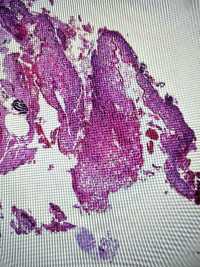

CIN1?

图1

图2

图3

图4

LSIL。

其实lsil的诊断一致性很低,上海的标准诊断lsil比较严格,似是而非者为非,本例属于似是而非,按我们的日常则争议比较多,我觉得综合看吧,阴道镜表现,hpv和tct检测结果来综合判断。

谢谢各位老师,TCT报ASCUS,患者自述HPV59阳